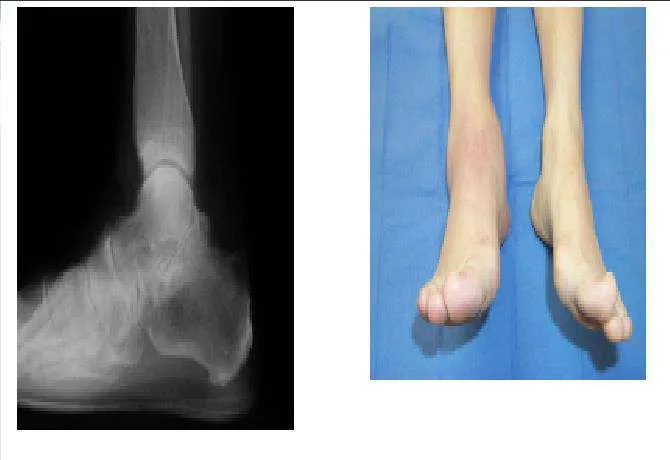

Question 48:

A 43-year-old woman has had a 2-year history of ankle pain. Her ankle pain is associated with swelling, decreased activities, and limited range of motion. Upon examination, diffuse warmth and swelling of the ankle are noted. Radiographs and a clinical picture are presented. The most likely diagnosis is:

Correct Answer: Rheumatoid arthritis

Explanation:

Although pigmented villonodular synovitis (PVNS), infection, or gout may cause inflammatory changes on both sides of the ankle joint, the most likely cause of this inflammatory arthropathy is rheumatoid arthritis. Note the cystic changes, the synovial hypertrophy, and the joint inflammation.